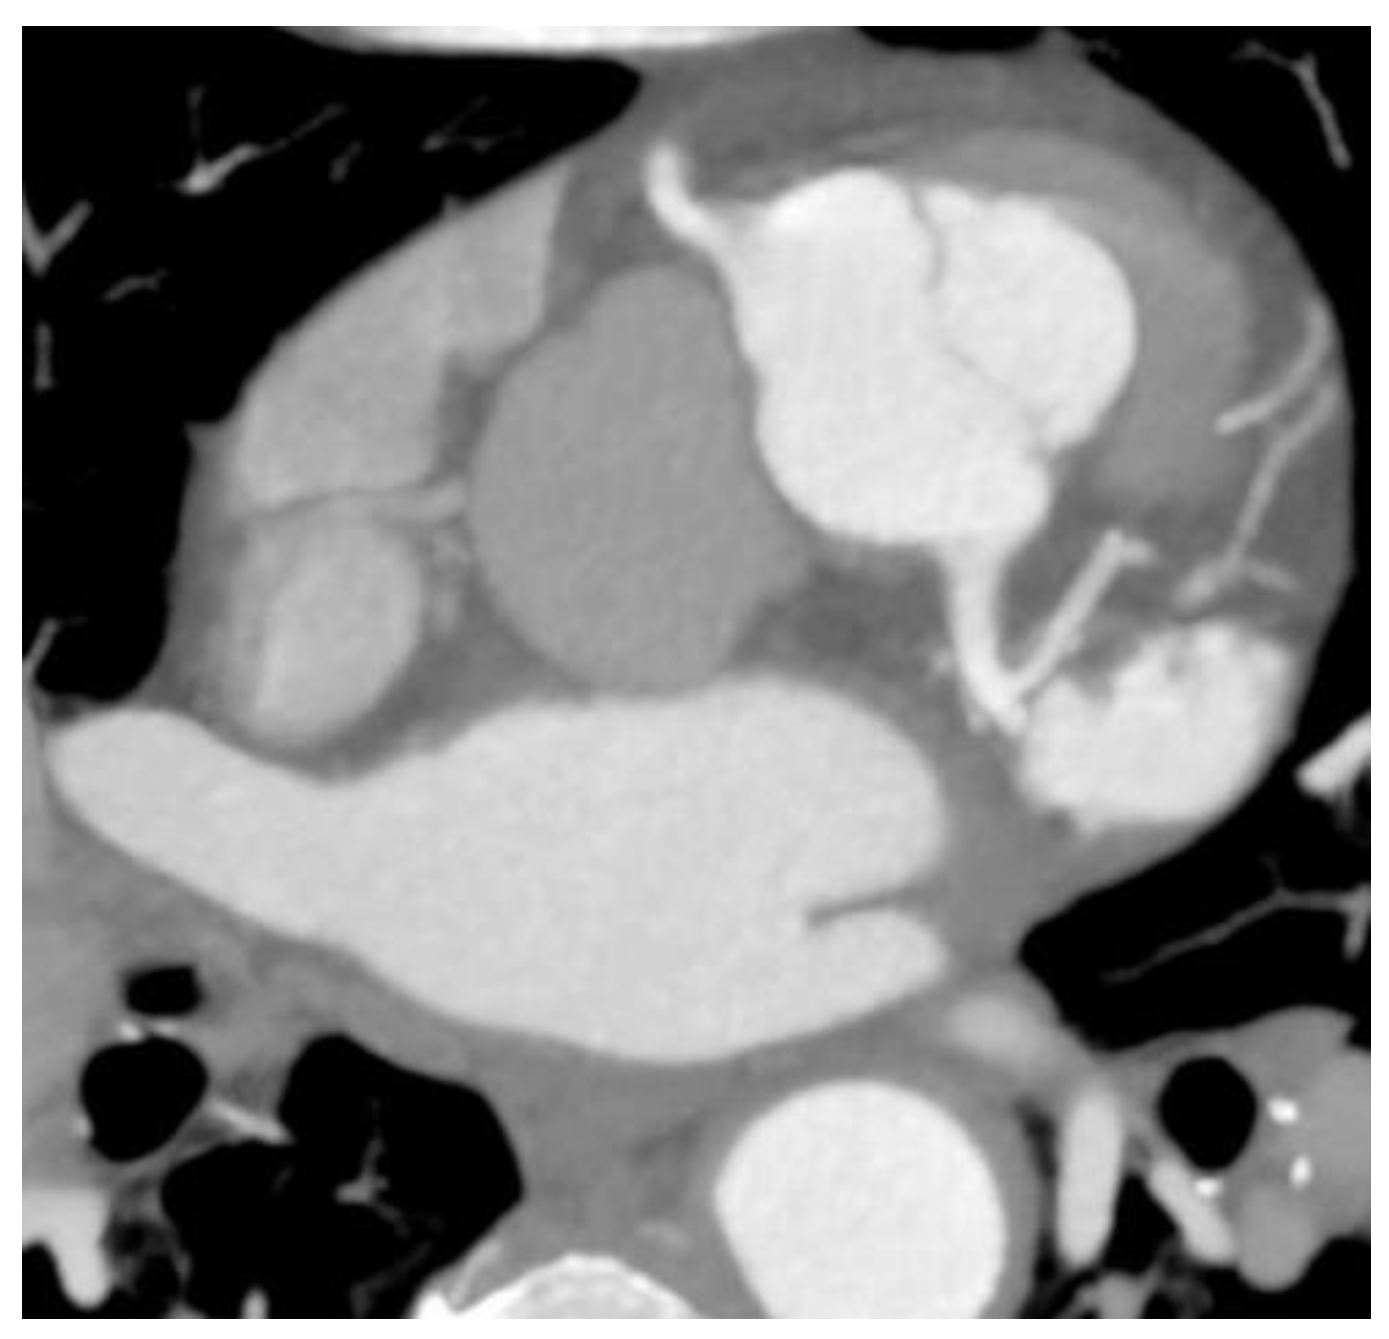

Two cases of anomalous origin of the left main coronary artery arising from the right sinus were found, as depicted in

Figure 1.

Two cases of a left coronary artery originating from the right coronary sinus were found; this is a rare anomaly; the prevalence of coronary artery anomalies arising from the opposite site in the scientific literature is between 0.1% and 0.2%, with the left coronary arising from the right sinus being six times rarer than the right coronary artery originating from the left sinus [

19]. This is considered an anomaly associated with a risk of sudden death estimated between 0.17% and 0.35% because of the larger myocardial territory associated with ischemic risk [

19,

20].